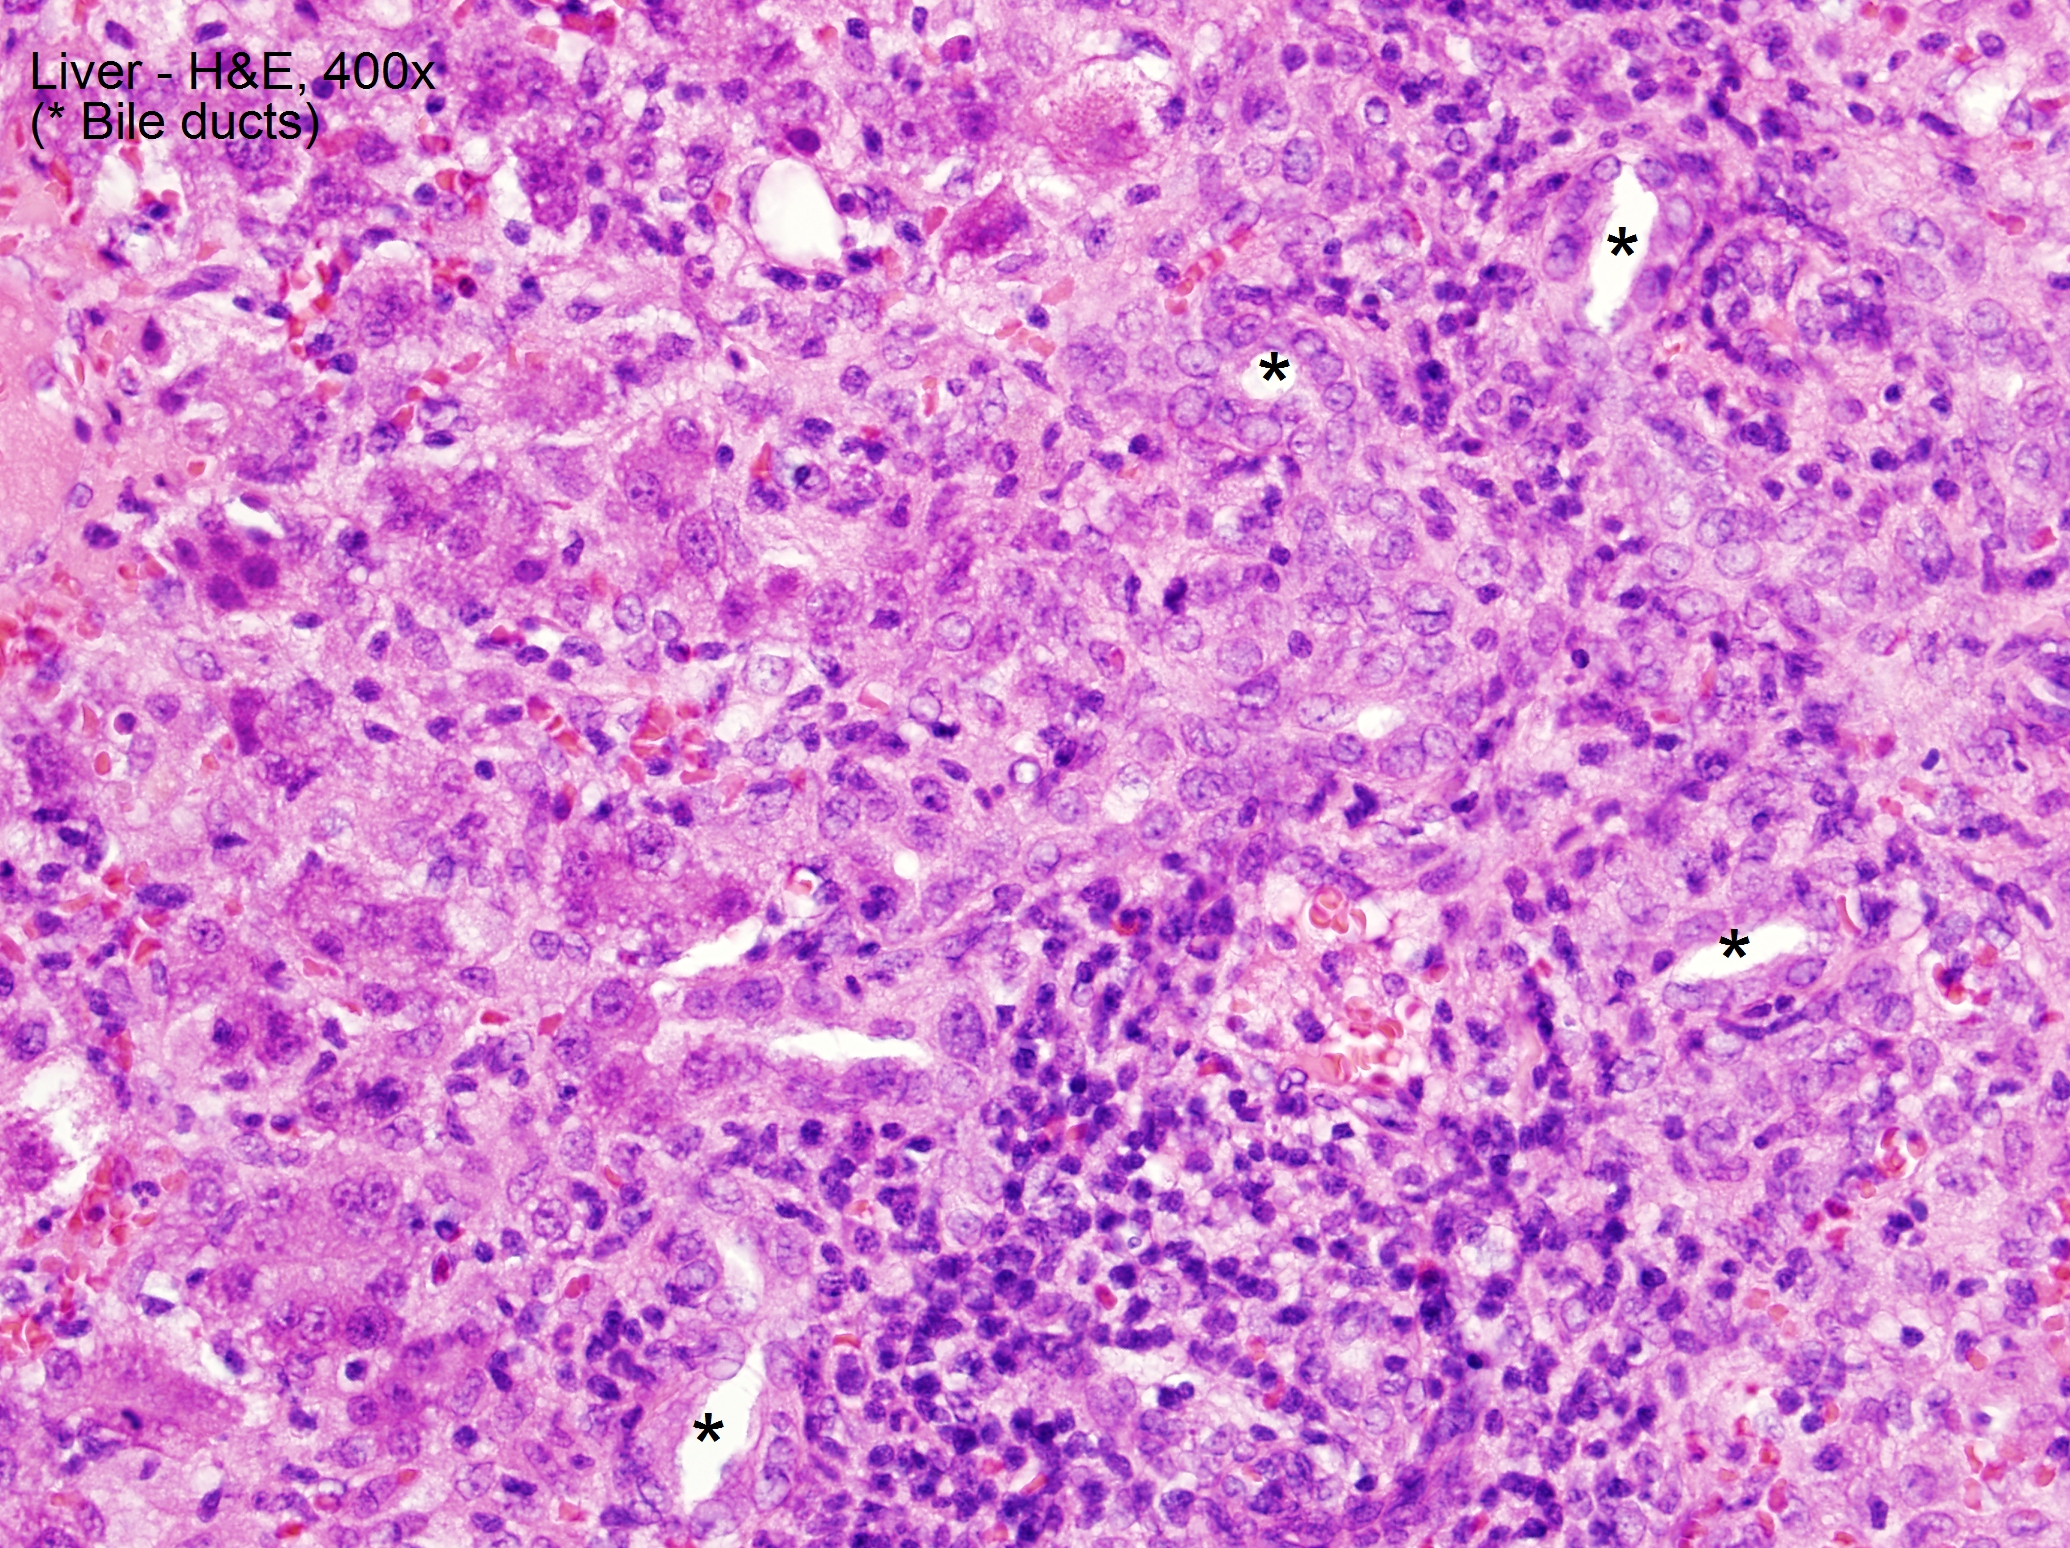

Case Presentation: We report a case of suspected sevoflurane hepatotoxicity in a 13-month-old male with repeated sevoflurane exposure. Prior to presentation, he was given sevoflurane as an inhaled anesthetic for 3 separate procedures related to Gtube removal and subsequent fistula and abscess formation. On presentation, he was found to be jaundiced and had scleral icterus. Labs revealed markedly elevated alkaline phosphatase (508), AST (1,500), ALT (1,869), total and direct bilirubin (5.3/3.8), PTT (40.2), and PT/INR (16.9/1.5). On day 3 of hospitalization, he underwent I&D under anesthesia and was exposed to sevoflurane again. After, he had a sharp increase in AST to peak >3,500. Multiple infectious disease titers and antibodies, tuberculin detection by T spot, and autoimmune work-up, including anti-smooth muscle antibody and anti-liver- kidney antibody, resulted as negative. Alpha -1 antitrypsin was within normal limits. Thyroid studies revealed a normal T4 (0.82) and slightly low TSH (0.28). Acetaminophen level on admission was <3. Liver biopsy demonstrated non-specific lobular and portal injury, characterized by giant-cell lobular changes and severe interface portal inflammation without necrosis or excessive copper or iron deposition. Our patient improved with conservative management.